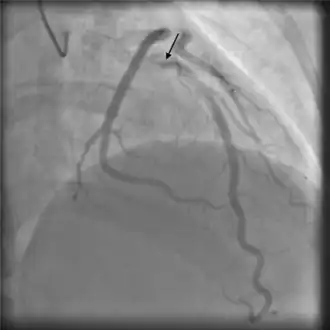

With typically elevated cardiac biomarkers and ECG changes, people will often undergo coronary angiography evaluation.[6][14][15] It is important to recognize SCAD through angiography as other confirmatory measures carry increased risks.[16]

Angiography

Angiographic appearances of SCAD fall into three categories.[13] Type 1 lesions appear as classic angiographic dissections, with a false lumen distinct from the true lumen. These are the easiest to identify as SCAD clinically, though relatively uncommon.[13] Type 2 lesions - the most common subtype of SCAD - appear as a long, smooth narrowing of the vessel without a distinctly visible false and true lumen.[6] Type 3 lesions appear similar to atherosclerotic lesions and are difficult to confirm as SCAD through angiography alone,[16] possibly requiring the use of intracoronary imaging.